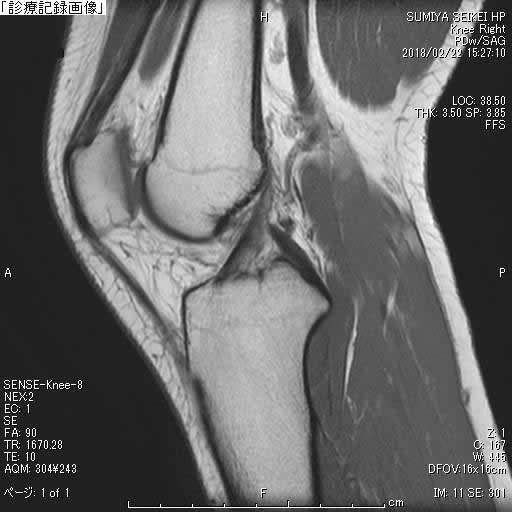

MRI

単純X線では初期の診断が困難な場合が多く、MRIでは軟骨変化の把握が可能なため有用です。